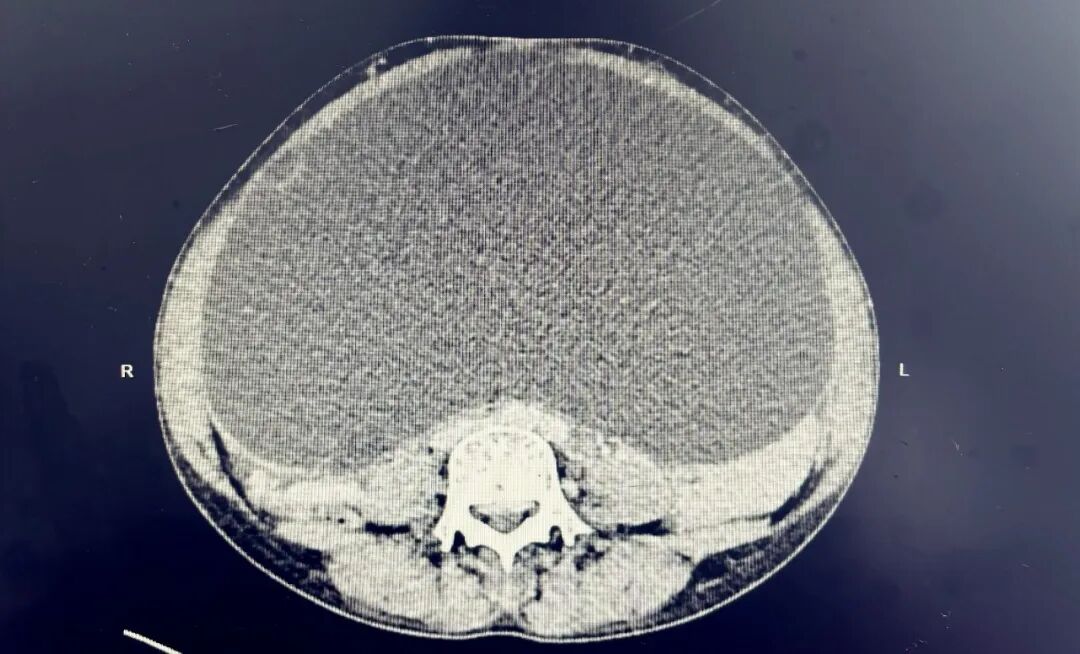

2026年3月20日,熊女士因“发现腹部增大伴腹胀5月余”入住我科。专科查体发现,其盆腔内可触及一巨大包块,上界达剑突下方,两侧延伸至腋前线,体积显著大于常见盆腔病变。该包块长期压迫腹腔及盆腔脏器,致使患者不适症状明显;加之包块性质尚不明确,暂无法排除卵巢或胃肠道来源肿瘤,这让患者及家属忧心忡忡、焦虑不已。

入院后,医疗团队迅速为熊女士完善血常规、肿瘤标志物、CT、MRI、胃镜等全面检查。结果显示:盆腔内为巨大多房囊性肿块,糖类抗原199等肿瘤指标升高;同时合并白细胞及中性粒细胞减少、幽门螺杆菌感染相关性胃炎、萎缩性胃炎,病情复杂,手术风险较高。